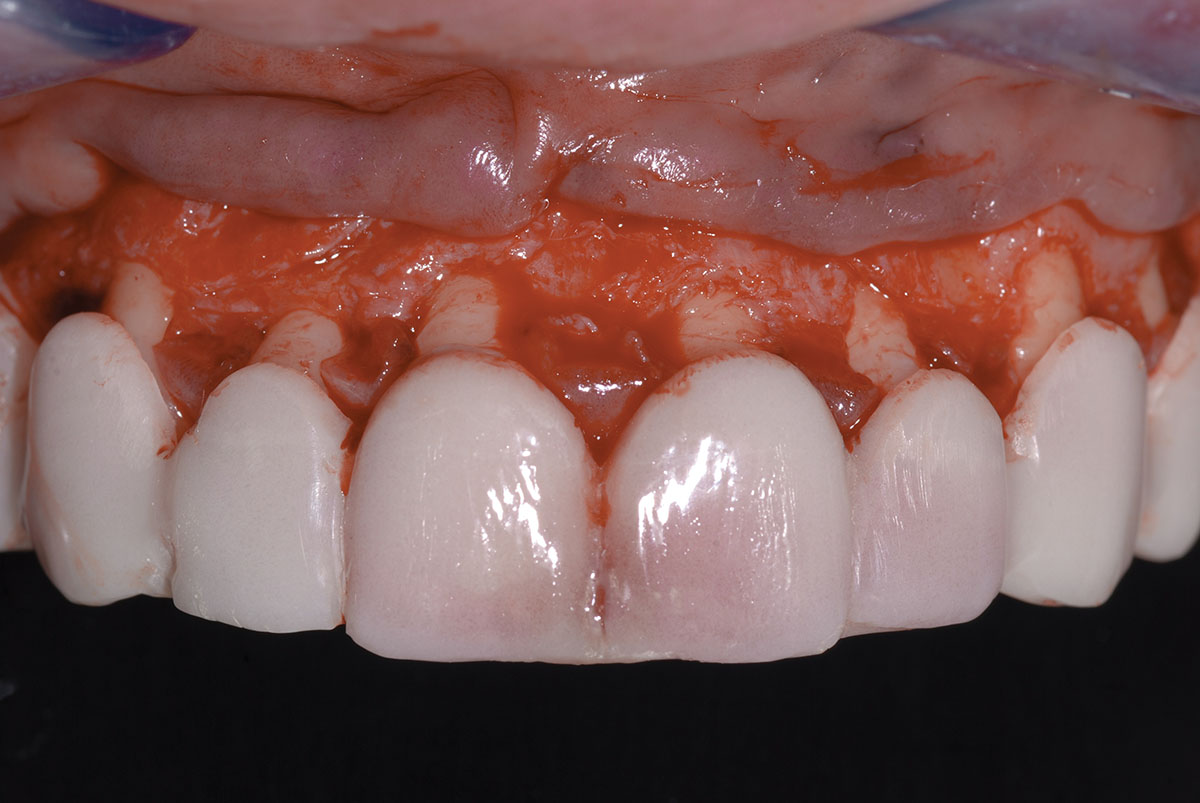

După anestezie, s-a practicat o incizie festonată la nivelul ţesutului gingival (fig. 3). În regiunea interproximală, s-a utilizat o incizie de prezervare a papilei (fig. 4). Osteoplastia şi ostectomia s-au realizat cu scopul de a poziţiona creasta osoasă la aproximativ 2-3mm de CEJ (fig. 5). Ţesutul gingival a fost repoziţionat să coincidă cu incizia labială iniţială şi cu papila interdentară. S-au folosit suturi întrerupte (fig. 6), care s-au îndepărtat după 7 zile.